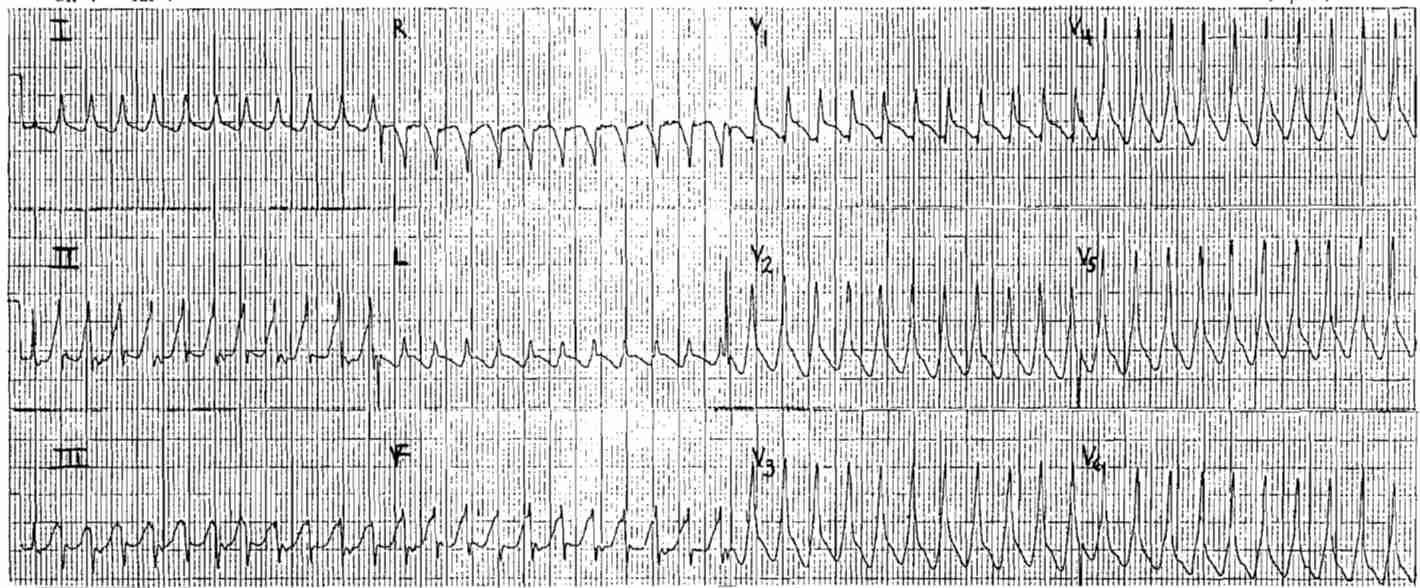

69 year-old man with dizziness.

What’s the rhythm ?